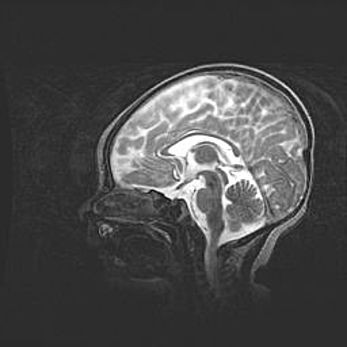

Церебральная ишемия II.

Возраст: 5 дней

Вес: 3400 г

Пол: женский

Окружность головы: 35 см

Срок гестации: 39 недель

Церебральная ишемия – это заболевание, характеризующееся недостаточностью (гипоксией) либо полным прекращением (аноксией) снабжения мозга кислородом по причине закупорки одного или нескольких сосудов. Это приводит к  что метаболическим расстройствам различной степени тяжести в тканях головного мозга, развитию коагуляционных некрозов и гибели нейронов.